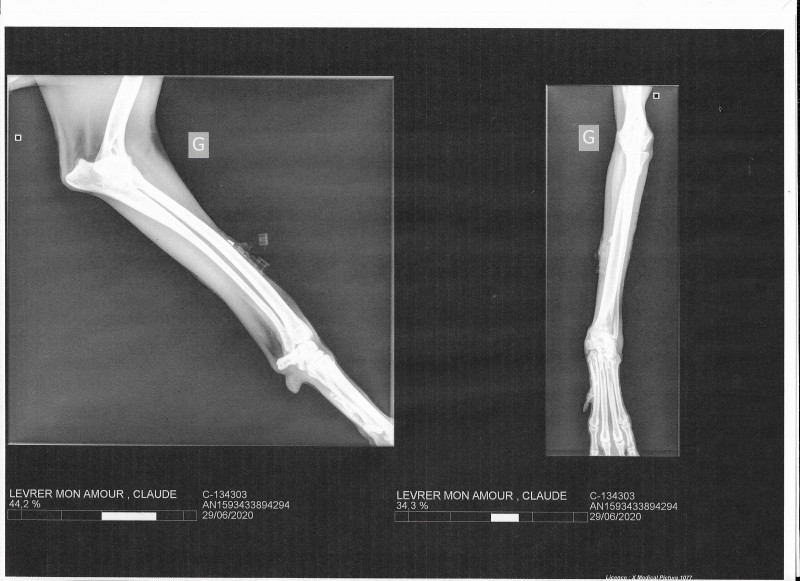

Claudya a vu un ostéopathe et nous avons consulté un spécialiste qui a fait des radios.

.jpg)

Claude (Claudya) a été retrouvée par des bénévoles espagnoles sans force avec de nombreuses blessures et dans un état de dénutrition avancé. Les vétérinaires espagnols pensaient qu’elle avait soit un cal osseux, une arthrose du dos ou une ancienne lésion. Il afallu du temps pour qu’elle récupère et elle vivait normalement.